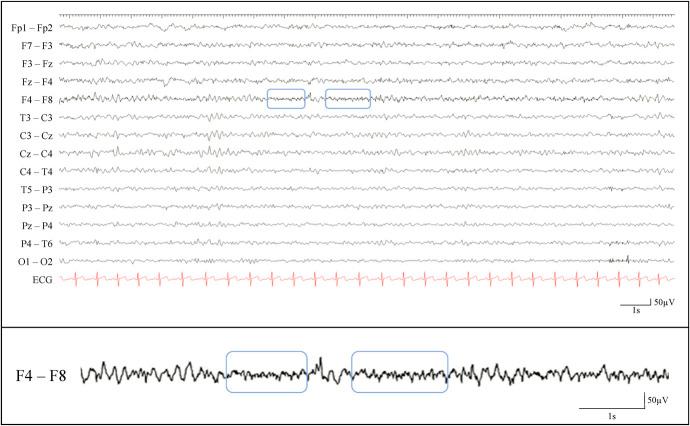

耐药性额叶癫痫中头皮脑电图的特征

The Fingerprint of Scalp-EEG in Drug-Resistant Frontal Lobe Epilepsies.

Scalp-EEG incompletely covers the frontal lobe cortex. Underrepresentation of frontobasal or frontomesial structures, fast ictal spreading, and false lateralization impede scalp-EEG interpretation. Hence, we investigated the significance of scalp-EEG in the presurgical workup of frontal lobe epilepsy.

Using descriptive statistical methods and Pearson chi-squared test for group comparisons, we retrospectively investigated postsurgical outcome, interictal epileptiform discharges (iiEDs), and electrographic seizure patterns on scalp-EEG in 81 consecutive patients undergoing resective epilepsy surgery within the margins of the frontal lobe.

Postoperatively, patients with frontopolar iiEDs ( n = 7) or concordant frontopolar iiED focus and seizure-onset ( n = 2) were seizure free ( n = 7/7, Engel Ia). MRI-positive patients with frontopolar iiEDs or frontopolar seizure-onset ( n = 1/8 Engel Id, n = 7/8 Engel Ia) underwent surgery without stereo-EEG. Thirteen of 16 patients with frontolateral ( n = 8/10, Engel Ia), or left frontobasal ( n = 5/6, Engel Ia) seizure-onset undergoing further stereo-EEG, were seizure-free postoperatively. Seizure-onset prevalent over one electrode ( n = 37/44 Engel I, p = 0.02), fast activity (FA)/flattening at seizure-onset ( n = 29/33 Engel I, p = 0.02), FA/flattening during the seizure ( n = 38/46 Engel I, p = 0.05), or focal rhythmic sharp-/spike-/polyspike-and-slow waves during the seizure ( n = 24/31, Engel Ia, p = 0.05) were favorable prognostic markers. Interictal polyspike waves ( p = 0.006 for Engel Ia) and interictal paroxysmal FA ( p = 0.02 for Engel I) were unfavorable prognostic markers.

Frontopolar scalp-EEG findings serve as biomarkers for predicting favorable surgical outcome in lesional frontal lobe epilepsy. Consequently, careful analysis of scalp-EEG assists in bypassing stereo-EEG in these patients.